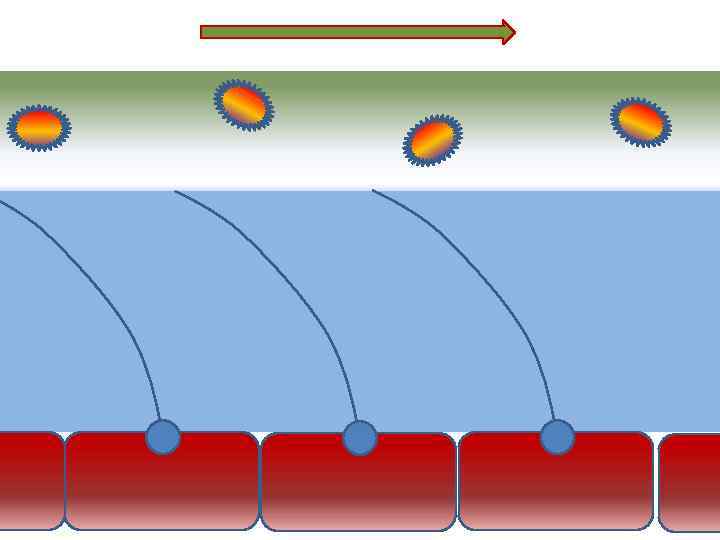

Факторы риска Недостаточное увлажнение дыхательной смеси • естественное удаление бактерий • состояние эпителия трахеи и бронхов

Факторы риска Недостаточное увлажнение дыхательной смеси • естественное удаление бактерий • состояние эпителия трахеи и бронхов

Оптимальное увлажнение 37°С, 44 мг/л Оптимальная влажность • Уменьшает время нахождения патогенной флоры в легком

Оптимальное увлажнение 37°С, 44 мг/л Оптимальная влажность • Уменьшает время нахождения патогенной флоры в легком

Механизм защиты легкого Слизь (зеленый цвет) нейтрализует и связывает патогенную флору(синий цвет) Слизь – это барьер между клетками и патогенной флорой Слизь – это транспортное средство

Механизм защиты легкого Слизь (зеленый цвет) нейтрализует и связывает патогенную флору(синий цвет) Слизь – это барьер между клетками и патогенной флорой Слизь – это транспортное средство